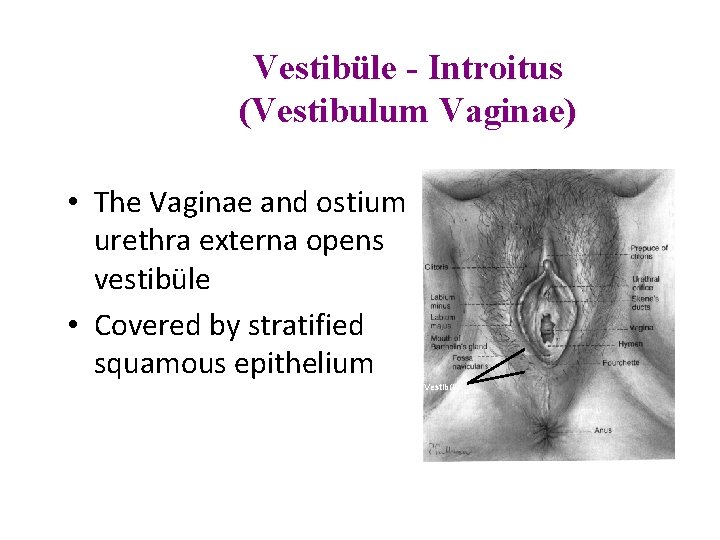

Vestibüle - Introitus (Vestibulum Vaginae) • The Vaginae and ostium urethra externa opens vestibüle • Covered by stratified squamous epithelium Vestibül